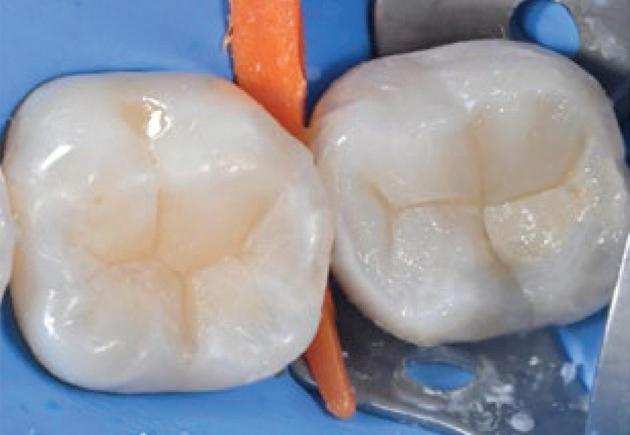

The Ivoclar Group is launching Tetric® plus, a new simplified composite specially designed to set new standards in universal composites. Tetric plus takes its name from the Greek prefix “tetra”, meaning “four” and this number is central to its key product features. It incorporates four essential elements: simplified shade matching with just 4 shades, increments of up to 4mm for greater efficiency, versatile application options in all 4 quadrants and an optimised 4-filler technology for excellent handling and aesthetic results.

Tetric plus revolutionises shade selection in dentistry, allowing for easy shade matching with its innovative colour cloud concept. Just 4 shades cover the entire spectrum of the classical VITA shades. Thanks to its exceptional shade adaptation, Tetric plus creates an outstanding chameleon effect: In its cured state, the material absorbs and scatters light in a way that closely mimics natural tooth structure, allowing it to blend almost seamlessly with the surrounding tooth structure. This high level of adaptation is achieved through the perfect combination of monomers, fillers and pigments.

Another remarkable feature of Tetric plus is its ability to accommodate variable layer thicknesses ranging from 0.1 to 4mm, allowing for greater flexibility while also reducing material consumption. Another notable advantage is its reliable curing time of just 3 seconds,1 that allows for a fast and easy application. These short curing times streamline workflows, minimise interruptions for dentists and enhance treatment efficiency. By enabling faster and more efficient restorations, Tetric plus not only saves valuable time but also improves the overall patient experience.

Tetric plus is a simplified universal composite that is suitable for all cavity classes, from Class I to V. With just one product, dentists can treat a wide range of indications in all 4 quadrants, significantly reducing material consumption and streamlining the workflow. For maximum handling convenience, Tetric plus is available in two viscosities: sculptable and flowable.

The quality of Tetric plus is defined by its innovative 4-filler technology, which integrates a combination of nano-

and micro-particles to deliver outstanding mechanical properties. Tetric plus ensures reliable curing for layers of up to 4mm while offering high radiopacity to facilitate accurate detection during diagnosis. The mechanical properties include high flexural strength (133 MPa), high compressive strength along with low wear and low shrinkage stress, reducing the risk of marginal gaps.

Tetric plus is more than just another composite: it is designed to simplify the daily workflow of dentists and optimise their treatment efficiency. With easy shade selection and short curing times, dentists can focus entirely on patient care, while delivering efficient and high-quality work. In summary, Tetric plus combines 4 shades with 4mm layer thicknesses, universal applicability in all 4 quadrants and an innovative 4-filler technology, making it the ideal solution for the demands of modern dentistry.